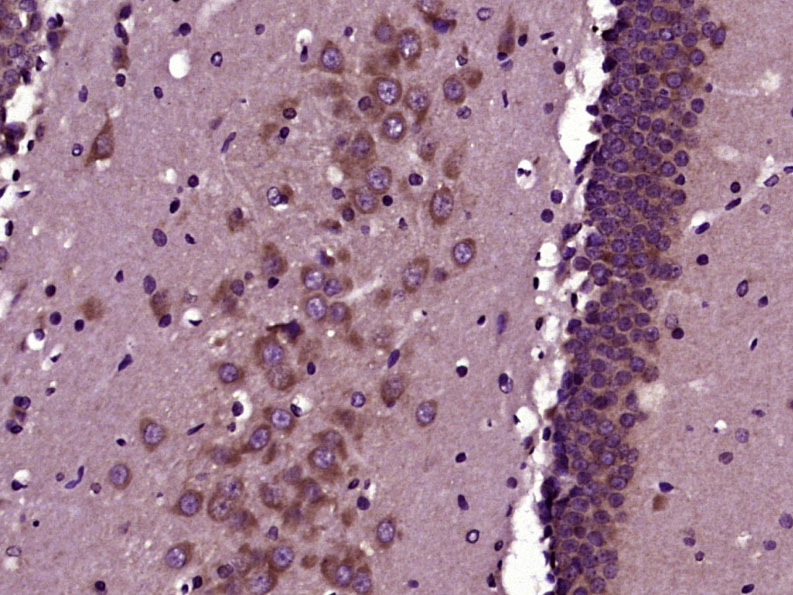

Paraformaldehyde-fixed, paraffin embedded (Rat brain); Antigen retrieval by boiling in sodium citrate buffer (pH6.0) for 15min; Block endogenous peroxidase by 3% hydrogen peroxide for 20 minutes; Blocking buffer (normal goat serum) at 37°C for 30min; Antibody incubation with (phospho-GAP43 (Ser41)) Polyclonal Antibody, Unconjugated (bs-1641R) at 1:400 overnight at 4°C, followed by operating according to SP Kit(Rabbit) (sp-0023) instructionsand DAB staining.

Paraformaldehyde-fixed, paraffin embedded (mouse cerebellum); Antigen retrieval by boiling in sodium citrate buffer (pH6.0) for 15min; Block endogenous peroxidase by 3% hydrogen peroxide for 20 minutes; Blocking buffer (normal goat serum) at 37°C for 30min; Antibody incubation with (phospho-GAP43 (Ser41)) Polyclonal Antibody, Unconjugated (bs-1641R) at 1:200 overnight at 4°C, followed by operating according to SP Kit(Rabbit) (sp-0023) instructionsand DAB staining.

Paraformaldehyde-fixed, paraffin embedded (rat cerebellum); Antigen retrieval by boiling in sodium citrate buffer (pH6.0) for 15min; Block endogenous peroxidase by 3% hydrogen peroxide for 20 minutes; Blocking buffer (normal goat serum) at 37°C for 30min; Antibody incubation with (phospho-GAP43 (Ser41)) Polyclonal Antibody, Unconjugated (bs-1641R) at 1:200 overnight at 4°C, followed by operating according to SP Kit(Rabbit) (sp-0023) instructionsand DAB staining.

Paraformaldehyde-fixed, paraffin embedded (mouse brain); Antigen retrieval by boiling in sodium citrate buffer (pH6.0) for 15min; Block endogenous peroxidase by 3% hydrogen peroxide for 20 minutes; Blocking buffer (normal goat serum) at 37°C for 30min; Antibody incubation with (phospho-GAP43 (Ser41)) Polyclonal Antibody, Unconjugated (bs-1641R) at 1:200 overnight at 4°C, followed by operating according to SP Kit(Rabbit) (sp-0023) instructionsand DAB staining.